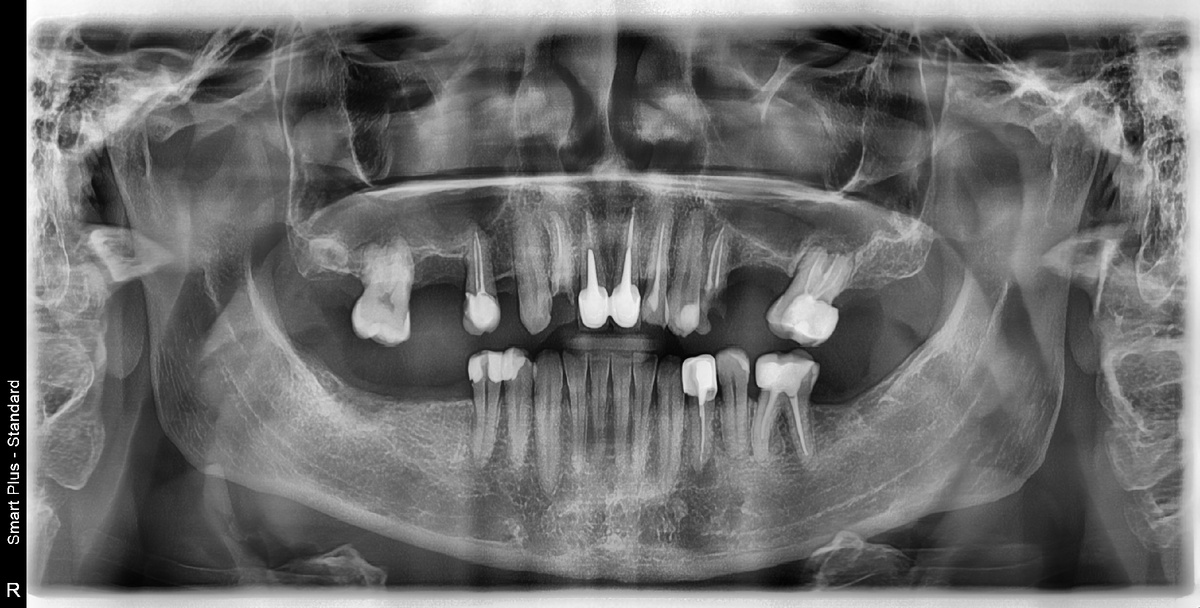

Пример панорамного рентген - снимка (снимок ОПТГ).

Панорамный рентгеновский снимок, или ОПТГ, позволяет врачу увидеть не только коронки зубов, но и внутренние процессы — воспаления у корней, кисты, гранулёмы, последствия неправильного лечения каналов, хронические очаги инфекции, скрытые переломы, патологические изменения костной ткани. Именно по этому снимку врач может точно сказать, какие зубы пригодны для протезирования, а какие требуют предварительного лечения или удаления. Без снимка любое протезирование — это работа вслепую.